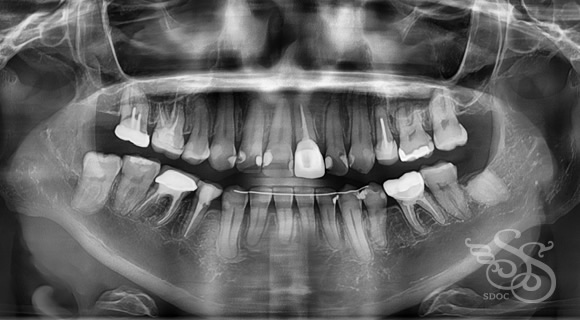

修復物が多い方の矯正

レントゲン:術前

レントゲン:術後